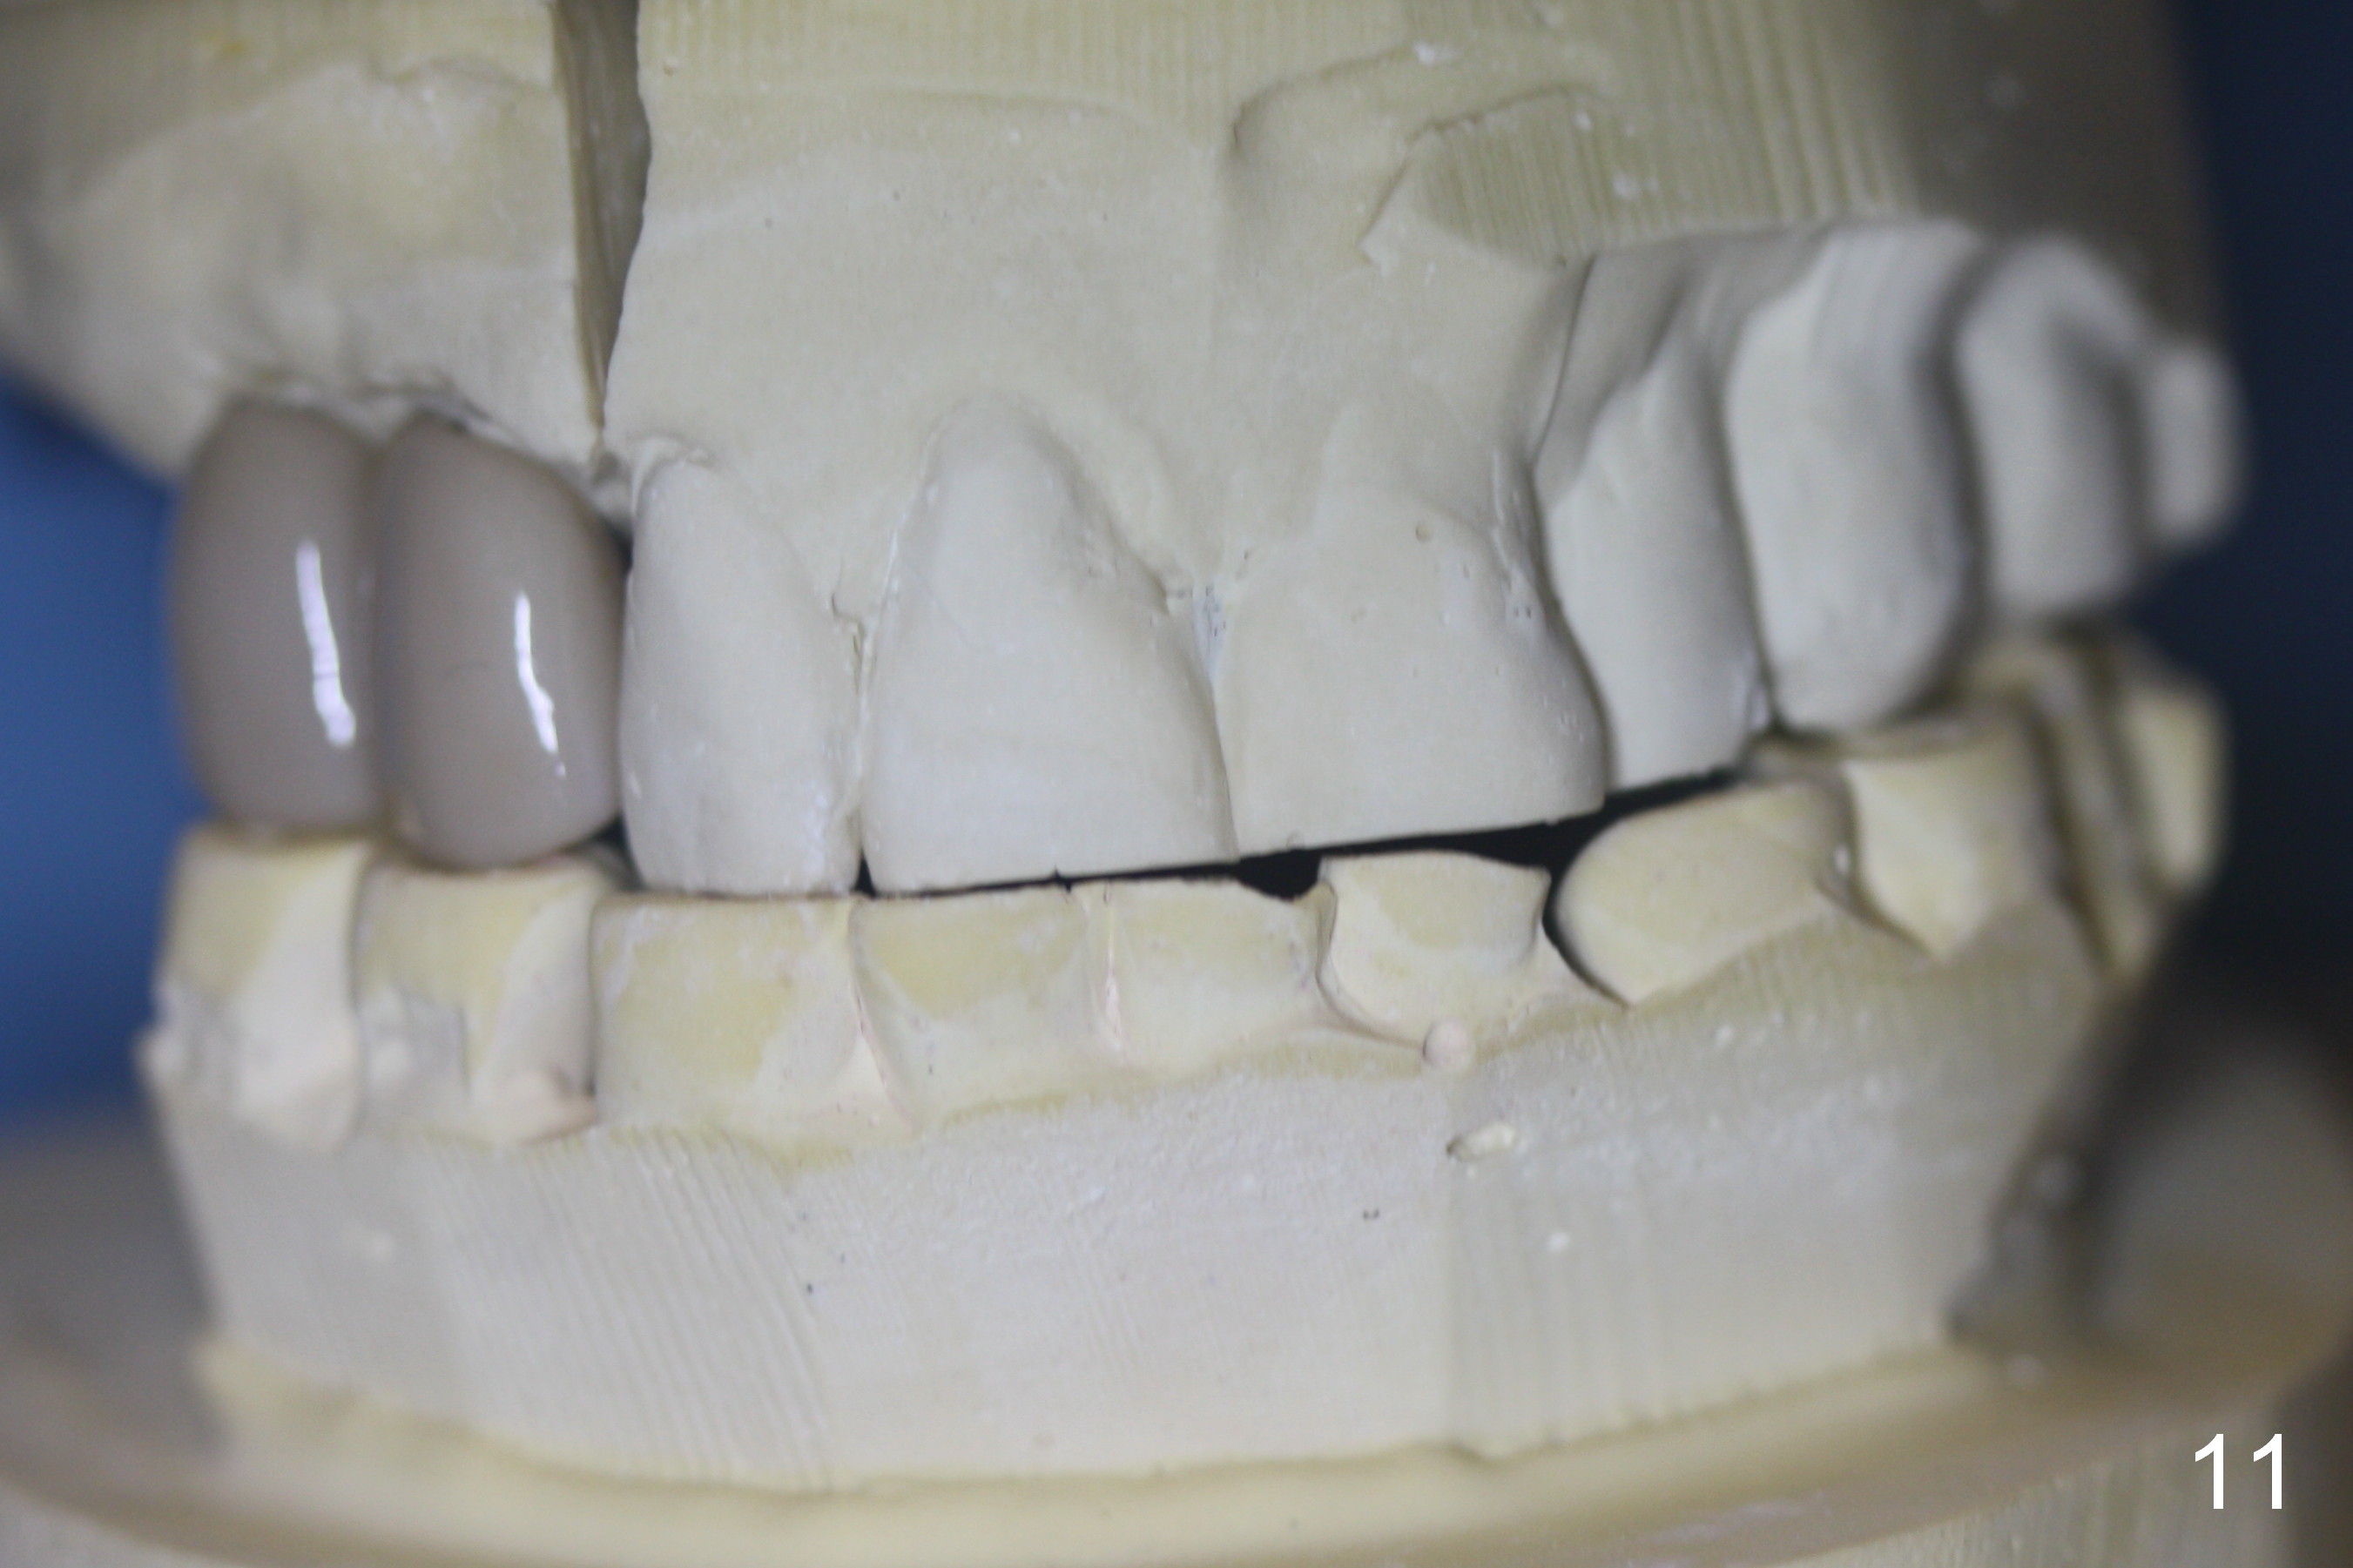

Bone density in the distal gap of #5 appears to have increased 3 months postop (Fig.7).  Prior to definitive restoration cementation (3.5 months postop), the buccal plate does not collapse (Fig.8).  There is no occlusal contact of the new restorations (Fig.9 *), probably due to bite discrepancy (Fig.10,11).